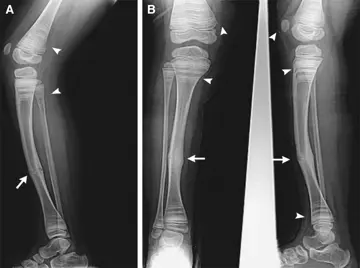

خطوط گورخری رادیوگرافی

یک پسربچه‌ی‌6‌ساله دچار نوعIV استئوژنزیس ایمپرفکتا را با درد ساق‌راست پس‌از افتادن به بخش اورژانس آوردند.